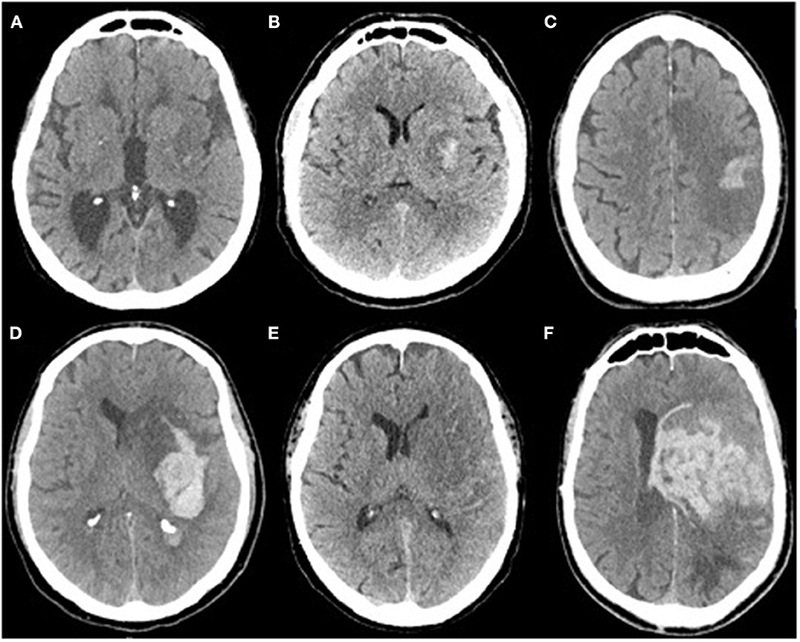

Khi bạn gặp bác sĩ, họ có thể xác định phần não nào bị ảnh hưởng dựa trên các triệu chứng của bạn. Các bác sĩ có thể thực hiện nhiều xét nghiệm hình ảnh khác nhau, chẳng hạn như chụp CT, có thể phát hiện chảy máu trong hoặc tích tụ máu hoặc chụp MRI. Khám thần kinh hoặc khám mắt, có thể cho thấy dây thần kinh thị giác bị phù, cũng có thể được thực hiện. Chọc dò thắt lưng thường không được thực hiện vì nó có thể nguy hiểm và khiến mọi việc trở nên tồi tệ hơn.